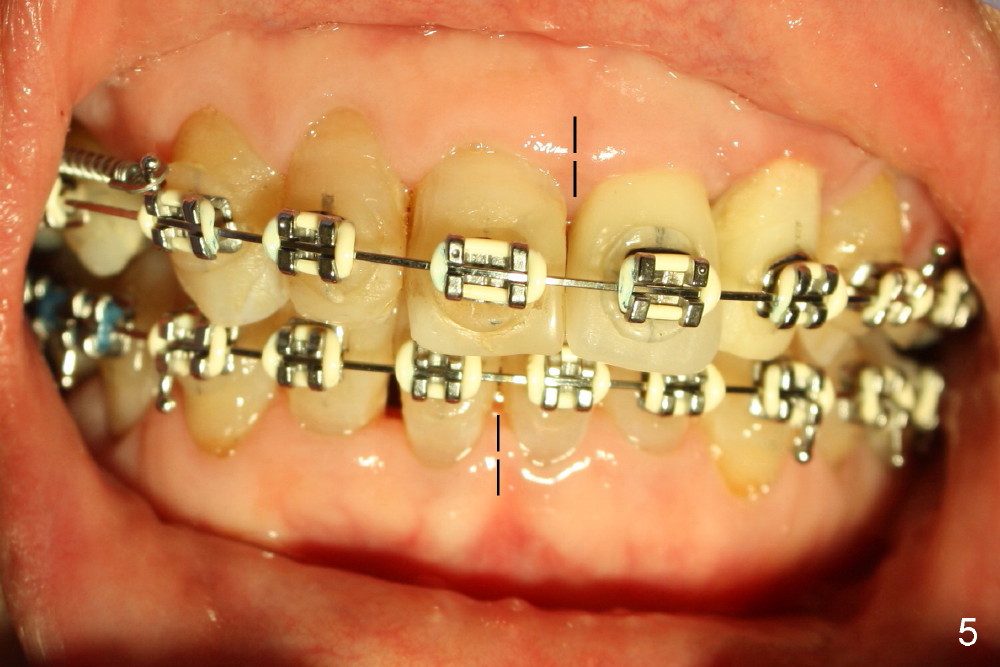

The upper midline seems to be deviated to the left (Fig.5 dashed lines). There is large anterior overjet (Fig.6 double arrows). The space between #4 and 6 (Fig.6,7 *) is to be closed by a closed spring between.#3 and 6, whereas the space mesial to #30 (Fig.4) will be closed by power chain between #28 and 30 (Fig.7) so that the tooth #27 has space to rotate and the distolingual caries is to be excavated (*).